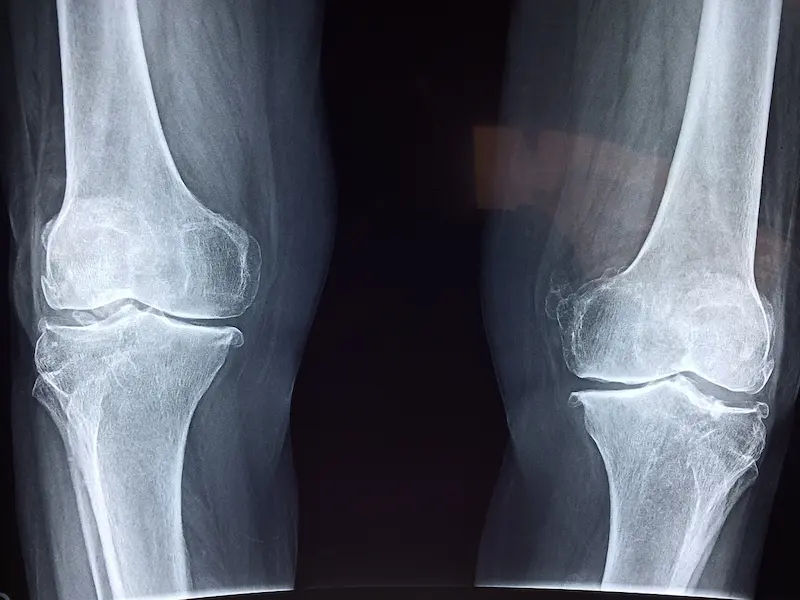

Imagen de Dr. Manuel González Reyes en Pixabay